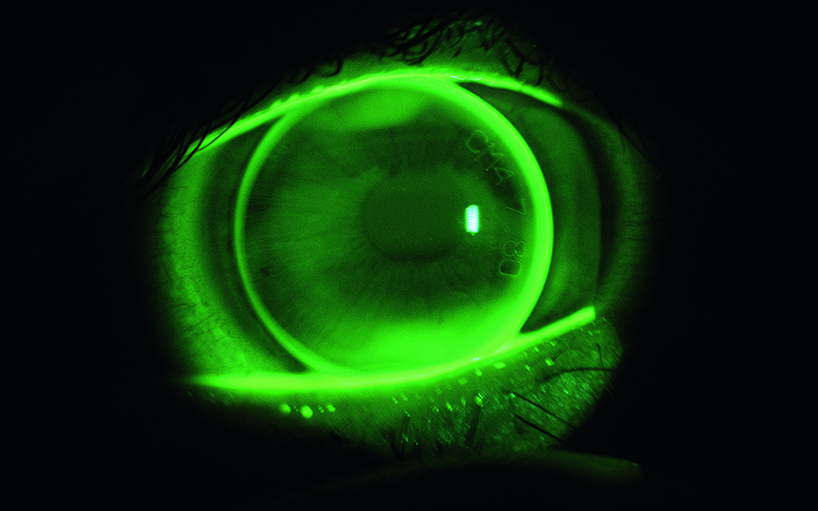

Development of a specialised contact lens with a built in pressure sensor for continuous determination of intraocular pressure.

The Institute of Optometry developed the contact lens geometry, enabling the physical intraocular pressure measurement and taking into account physiological compatibility with the eye.